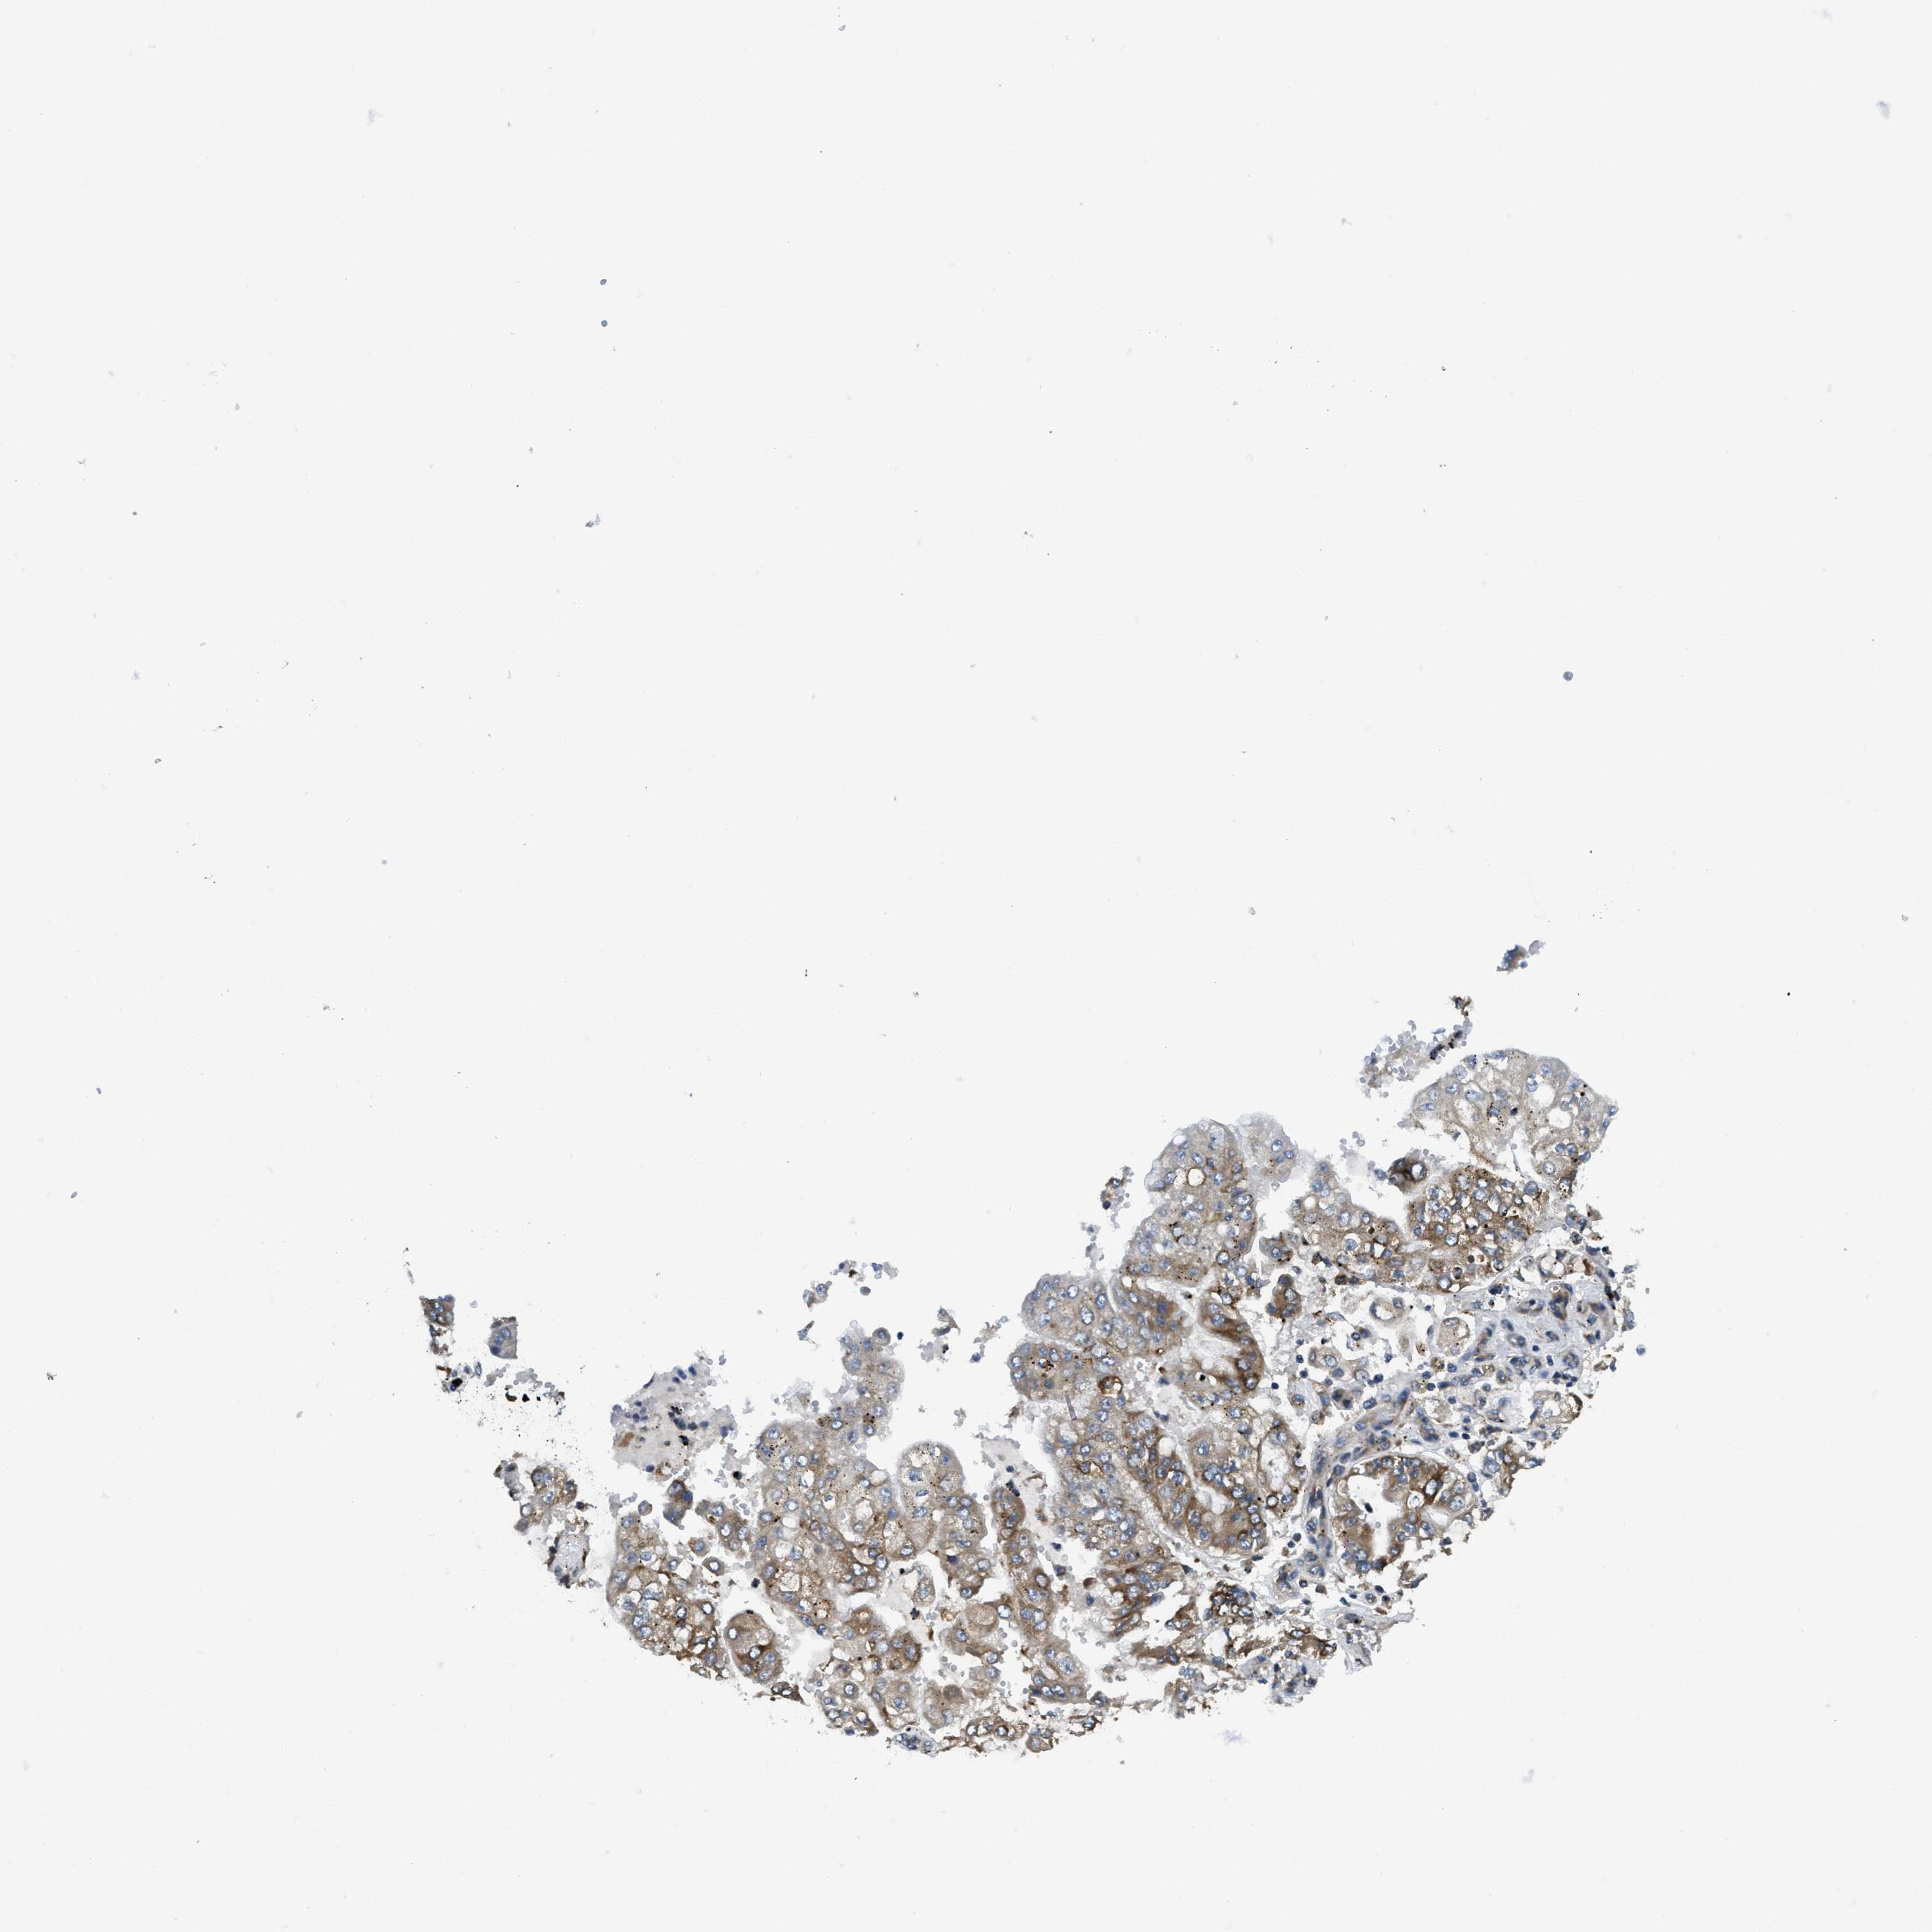

STOMACH CANCER - Protein expressioni

A mouse-over function shows sample information and annotation data. Click on an image to view it in a full screen mode. Samples can be filtered based on level of antibody staining by selecting one or several of the following categories: high, medium, low and not detected. The assay and annotation is described here.

Note that samples used for immunohistochemistry by the Human Protein Atlas do not correspond to samples in the TCGA dataset.

Antibody stainingi

Antibody staining in the annotated cell types in the current human tissue is reported as not detected, low, medium, or high, based on conventional immunohistochemistry profiling in selected tissues. This score is based on the combination of the staining intensity and fraction of stained cells.

Each image is clickable and will lead to virtual microscopy that enables deeper exploration of all samples and also displays staining intensity scores, fraction scores and subcellular localization as well as patient and tissue information for each sample.

Antibody HPA017062

Staining

High

Medium

Low

Not detected

Intensity

Strong

Moderate

Weak

Negative

Quantity

>75%

75%-25%

<25%

None

Location

Nuclear

Cytoplasmic/membranous

Cytoplasmic/membranous,nuclear

Adenocarcinoma, NOS

Adenocarcinoma, High grade